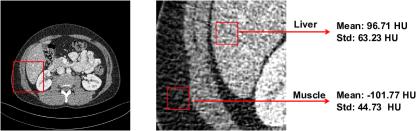

To address this issue, a few studies [23, 26] used a structural similarity (SSIM) loss or a perceptual loss [11]. However, they all perform in a sample-to-sample manner and ignore the inherent anatomical semantics, which could blur details in areas with low noise levels. Previous studies have shown that the level of noise in CT images varies depending on the type of tissues [17]; see an example in Fig. S1 in Supplementary Materials. Therefore, it is crucial to characterize the anatomical semantics for effectively denoising diverse tissues.

Figure S1: The mean and standard deviation of different tissues in an example of an LDCT image. The standard deviation (std) of an ROI in the liver is 63.23 HU, while the std of an ROI in the muscle is 44.73 HU.